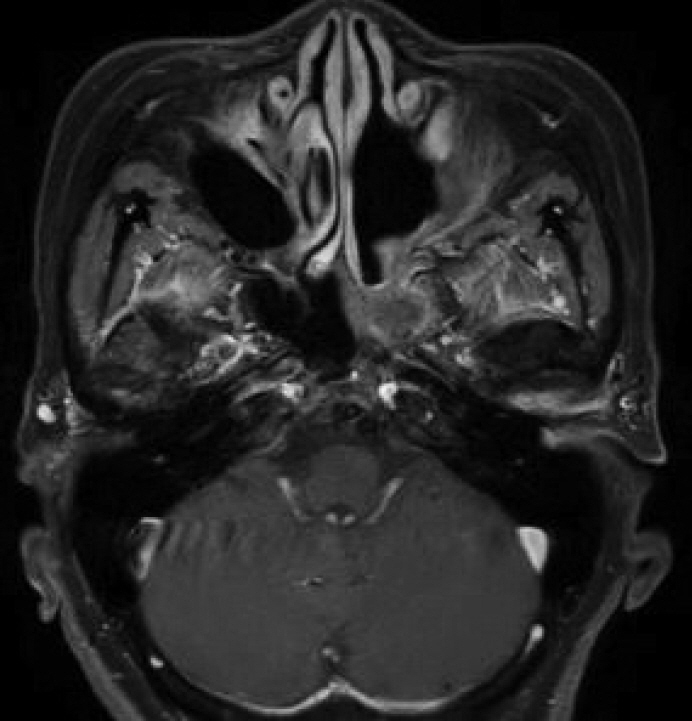

- Schwannomas are benign tumors that can develop in any part of a nerve containing Schwann cells. Skull base schwannomas are rare, representing approximately 4% of extracranial schwannomas. Among these, vidian nerve schwannomas are particularly uncommon, with only a few documented cases. In this report, we describe the case of a 58-year-old female patient who presented with an incidental finding of a skull base mass. The patient’s only symptoms were intermittent headaches and dry eyes. No mass was detected during the physical examination. Radiographic evaluation revealed a neoplasm within the vidian canal, and the lesion’s characteristics suggested a schwannoma. The patient underwent endoscopic resection, and subsequent histopathological analysis confirmed the diagnosis of schwannoma. Follow-up imaging and physical examination showed no evidence of recurrence. This case report highlights a schwannoma located in the vidian canal and extending into the foramen rotundum, which was successfully managed with endoscopic surgery.